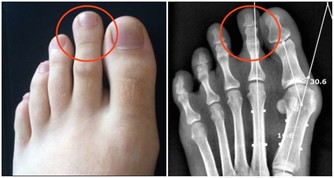

是由於變老的生理變化和病理變化,使患病的機率升高,衰老本身就是許多疾病的風險因素。

但是機體的這些病理變化,在沒有達到一定量的時候可以不發病;

只有病理變化累積達到一定程度,機體自身無法修復或及時修復的時候,才會出現生病的症狀。